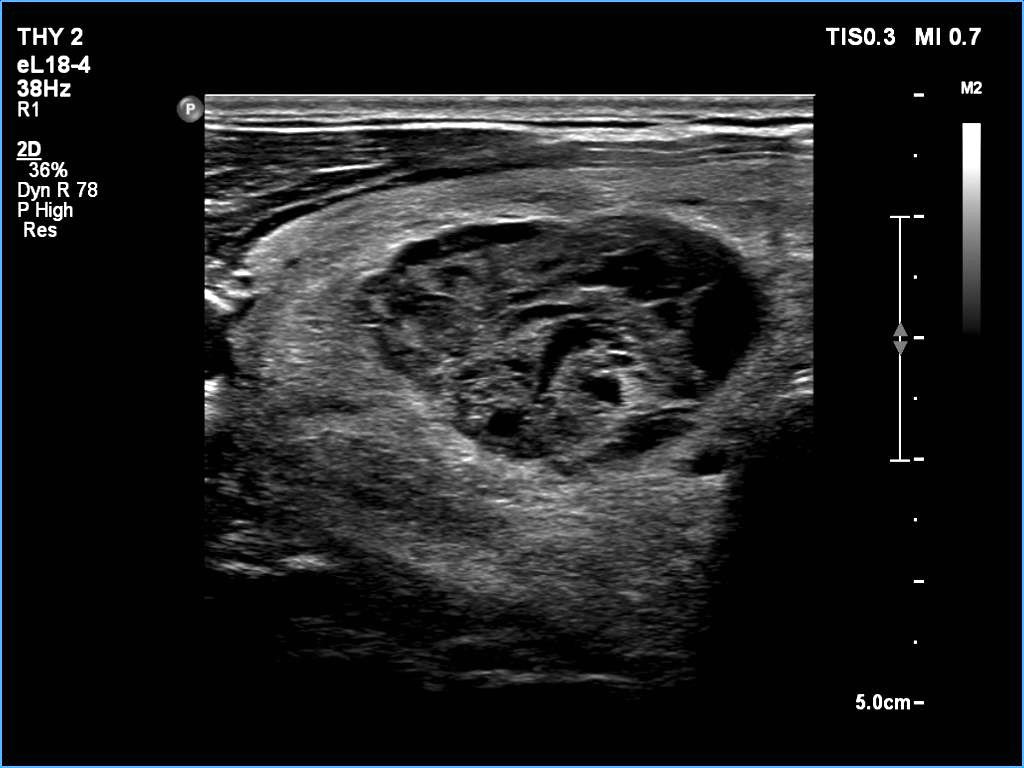

Ultrasonography: The thyroid was echonormal. There was a larger nodular mass in the right lobe which was composed of a dominantly solid echonormal portion that surrounded a dominantly cystic area. There were multiple nodules in the left lobe. The latter included an almost completely cystic lesion.

Comment. The right nodule is dominantly solid one because the cystic portion is less than 50%. The cystic portion of the nodule is multichambered which presents spongiform areas. The left cystic nodule is an almost completely cystic lesion, that has disappeared after the removal of cystic fluid.